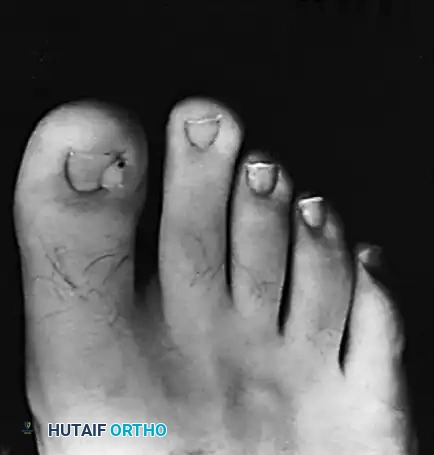

Clinical presentation of multiple periungual fibromas (Koenen tumors) characteristic of tuberous sclerosis.